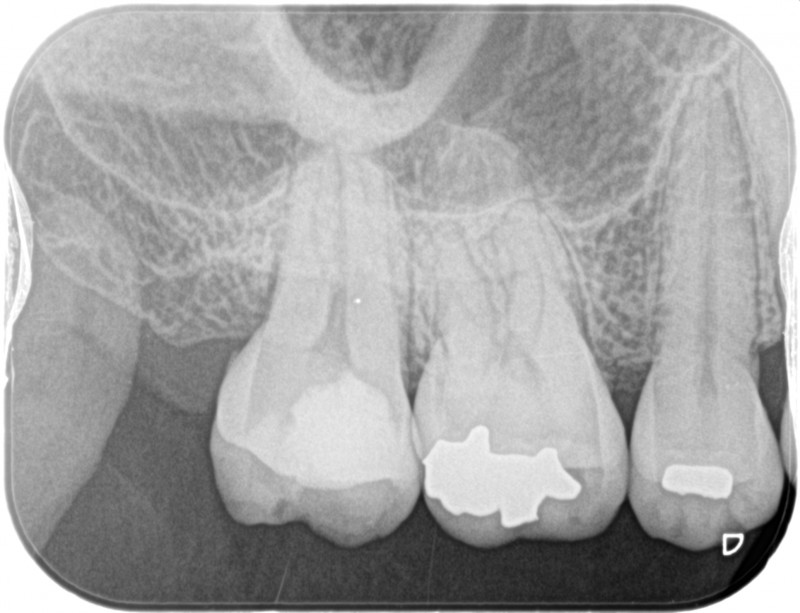

レントゲンの、赤丸のところが虫歯になっています。神経に届きそうなほど深いです。

1年後のレントゲン写真です。痛みも無く、詰め物の状態も安定しています。